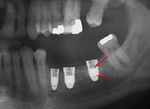

قبل زراعة الأسنان، يطلب من المريض اجراء فحص تصوير للأسنان، وعادة يطلب اجراء صورة خاصة (صورة أشعة بانوراما للأسنان) أو حتى فحص التصوير المقطعي المحوسب (CT)، للكشف والتشخيص عن حالات الأسنان التي ليس بالامكان رؤيتها من خلال الفحص الاعتيادي.